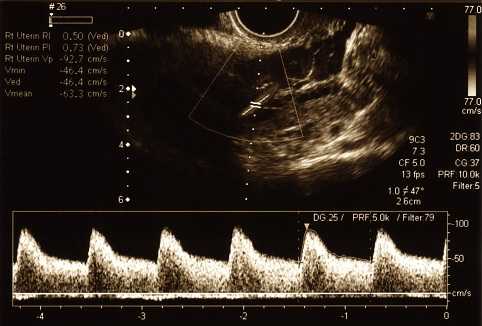

В акушерстве кардиотокография используется для регистрации сердечной деятельности плода и маточных сокращений, как правило, в третьем триместре беременности. Аппарат для мониторинга называется кардиотокограф или электронный фетальный монитор (EFM).

Одновременная запись осуществляется двумя отдельными преобразователями, один для измерения частоты сердечных сокращений плода, второй - для регистрации маточных сокращений. Каждый из датчиков может быть внешним или внутренним.

Внешние средства измерения представлены лентой (ремнем) на передней брюшной стенке. Кардиальный ультразвуковой датчик непрерывно излучает ультразвуковые волны и определяет движения сердца плода по отраженному звуку. Чувствительный к давлению трансдуцер, именуемый токодинамометр, имеет плоский участок, который фиксируется на коже живота.

Внутренние измерения требуют определенной степени расширения шейки матки, так как в нее вставляется катетер, измеряющий давление. Все это сочетается с электродами для головки плода, которые способны непрерывно отслеживать электрическую активность сердца плода в процессе родов. Внутренние измерения более точные и более предпочтительны при осложненных родах.